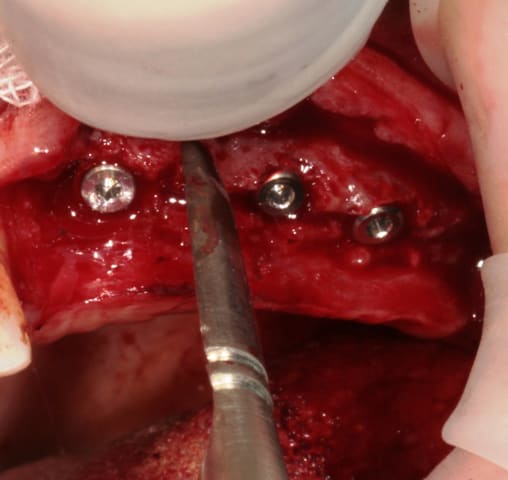

mise en place du conique lisse

L'outil de CLIO

contrôle, axe et profondeur